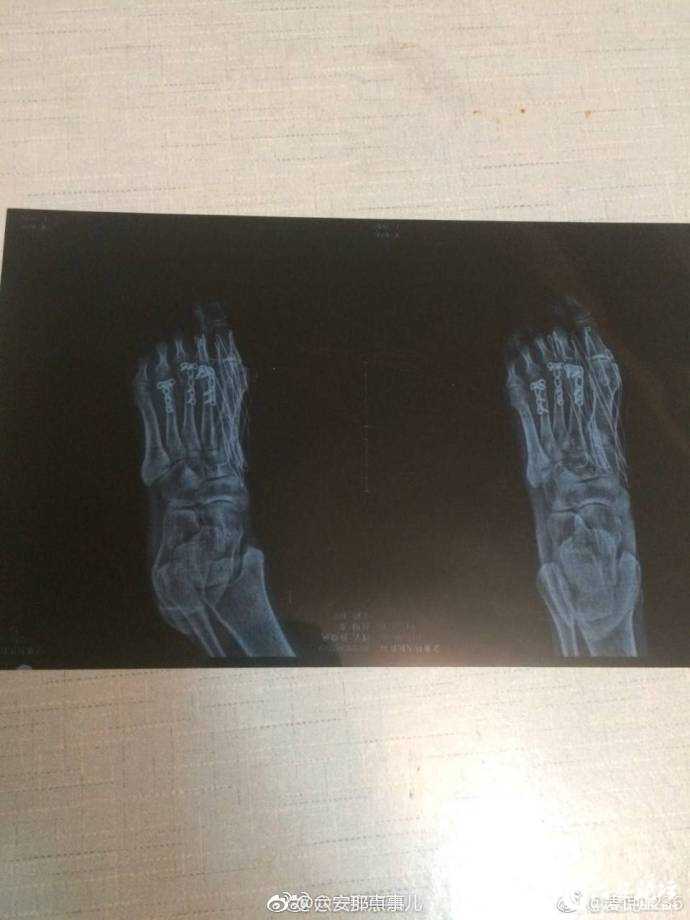

网友爆料:在金寨江店金江新城小区散步时,路面一处井盖破损,周围也没有任何警示标志,不慎在此处跌倒受伤,医生诊断其三根脚趾骨严重错位断裂。在此期间医疗费用更是多达两万余元!维权之路艰辛又漫长。小编发现,该网友在书记信箱里也发表过意见,希望能得到妥善处理。事儿妈要提醒下大家:

六安

城区也有很多破损井盖,都存在很大的安全隐患!走路时,要多注意!